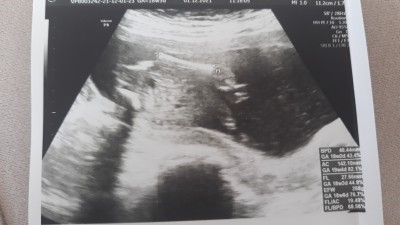

Geçen hafta kontrole gittim. Doktorum süpriz olsun şimdilik söylemeyeceğim dedi bende ısrar etmedim . Şimdi çok merak ettim tahmin edebilen anlayan var mı hanımlar

Gebelik haftası 19+1